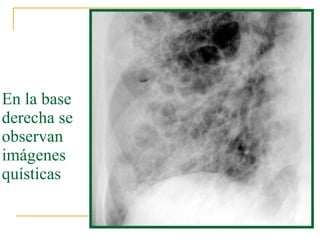

Extenso enfisema buloso en los lóbulos superiores de ambos pulmones.

Hacia las bases hay aumento de la densidad radiológica

En la base derecha se observan imágenes quísticas